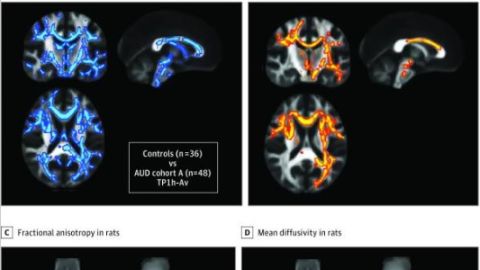

El estudio traslacional demuestra que hay una mayor difusividad media en la materia gris cerebral de los seres humanos y ratas que beben habitualmente. Estas alteraciones aparecen poco después del inicio del consumo de alcohol en ratas, persisten en la abstinencia temprana tanto en roedores como en humanos, y se asocian con una fuerte disminución de las barreras del espacio extracelular explicada por una reacción de la microglia a un agente agresor como el alcohol.